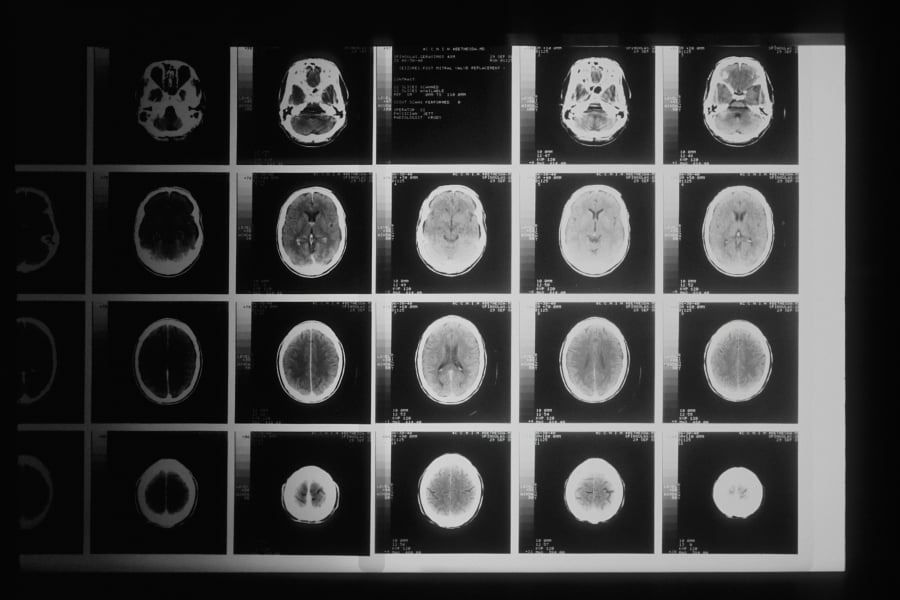

L’imagerie cérébrale est souvent perçue comme un domaine complexe et long, nécessitant un haut degré de précision et une manipulation délicate. Cela implique de passer de longues périodes exposé à des radiations. Récemment, un robot chirurgical chinois est venu alléger cette tâche, se révélant plus rapide que les intervenants humains.

Un rapport publié par le South China Morning Post a indiqué que ce système d’assistance robotique a permis de réduire le temps de la procédure d’environ 29 % lors des tests effectués à l’Hôpital de l’Université Médicale de Pékin. Lors d’une procédure standard, un chirurgien utilisant ce système a réussi à gagner neuf minutes par rapport aux techniques manuelles.

Des recherches supplémentaires rapportées par Scienmag ont révélé que ce système a été testé sur 50 patients, répartis équitablement entre interventions robotiques et manuelles. Les deux groupes ont réussi à obtenir un taux de succès de 100 % en ce qui concerne le positionnement et l’imagerie, sans complications notables. En moyenne, les procédures réalisées par le robot ont pris 27 minutes, contre 38 minutes pour les cas manuels, confirmant ainsi les économies de temps.